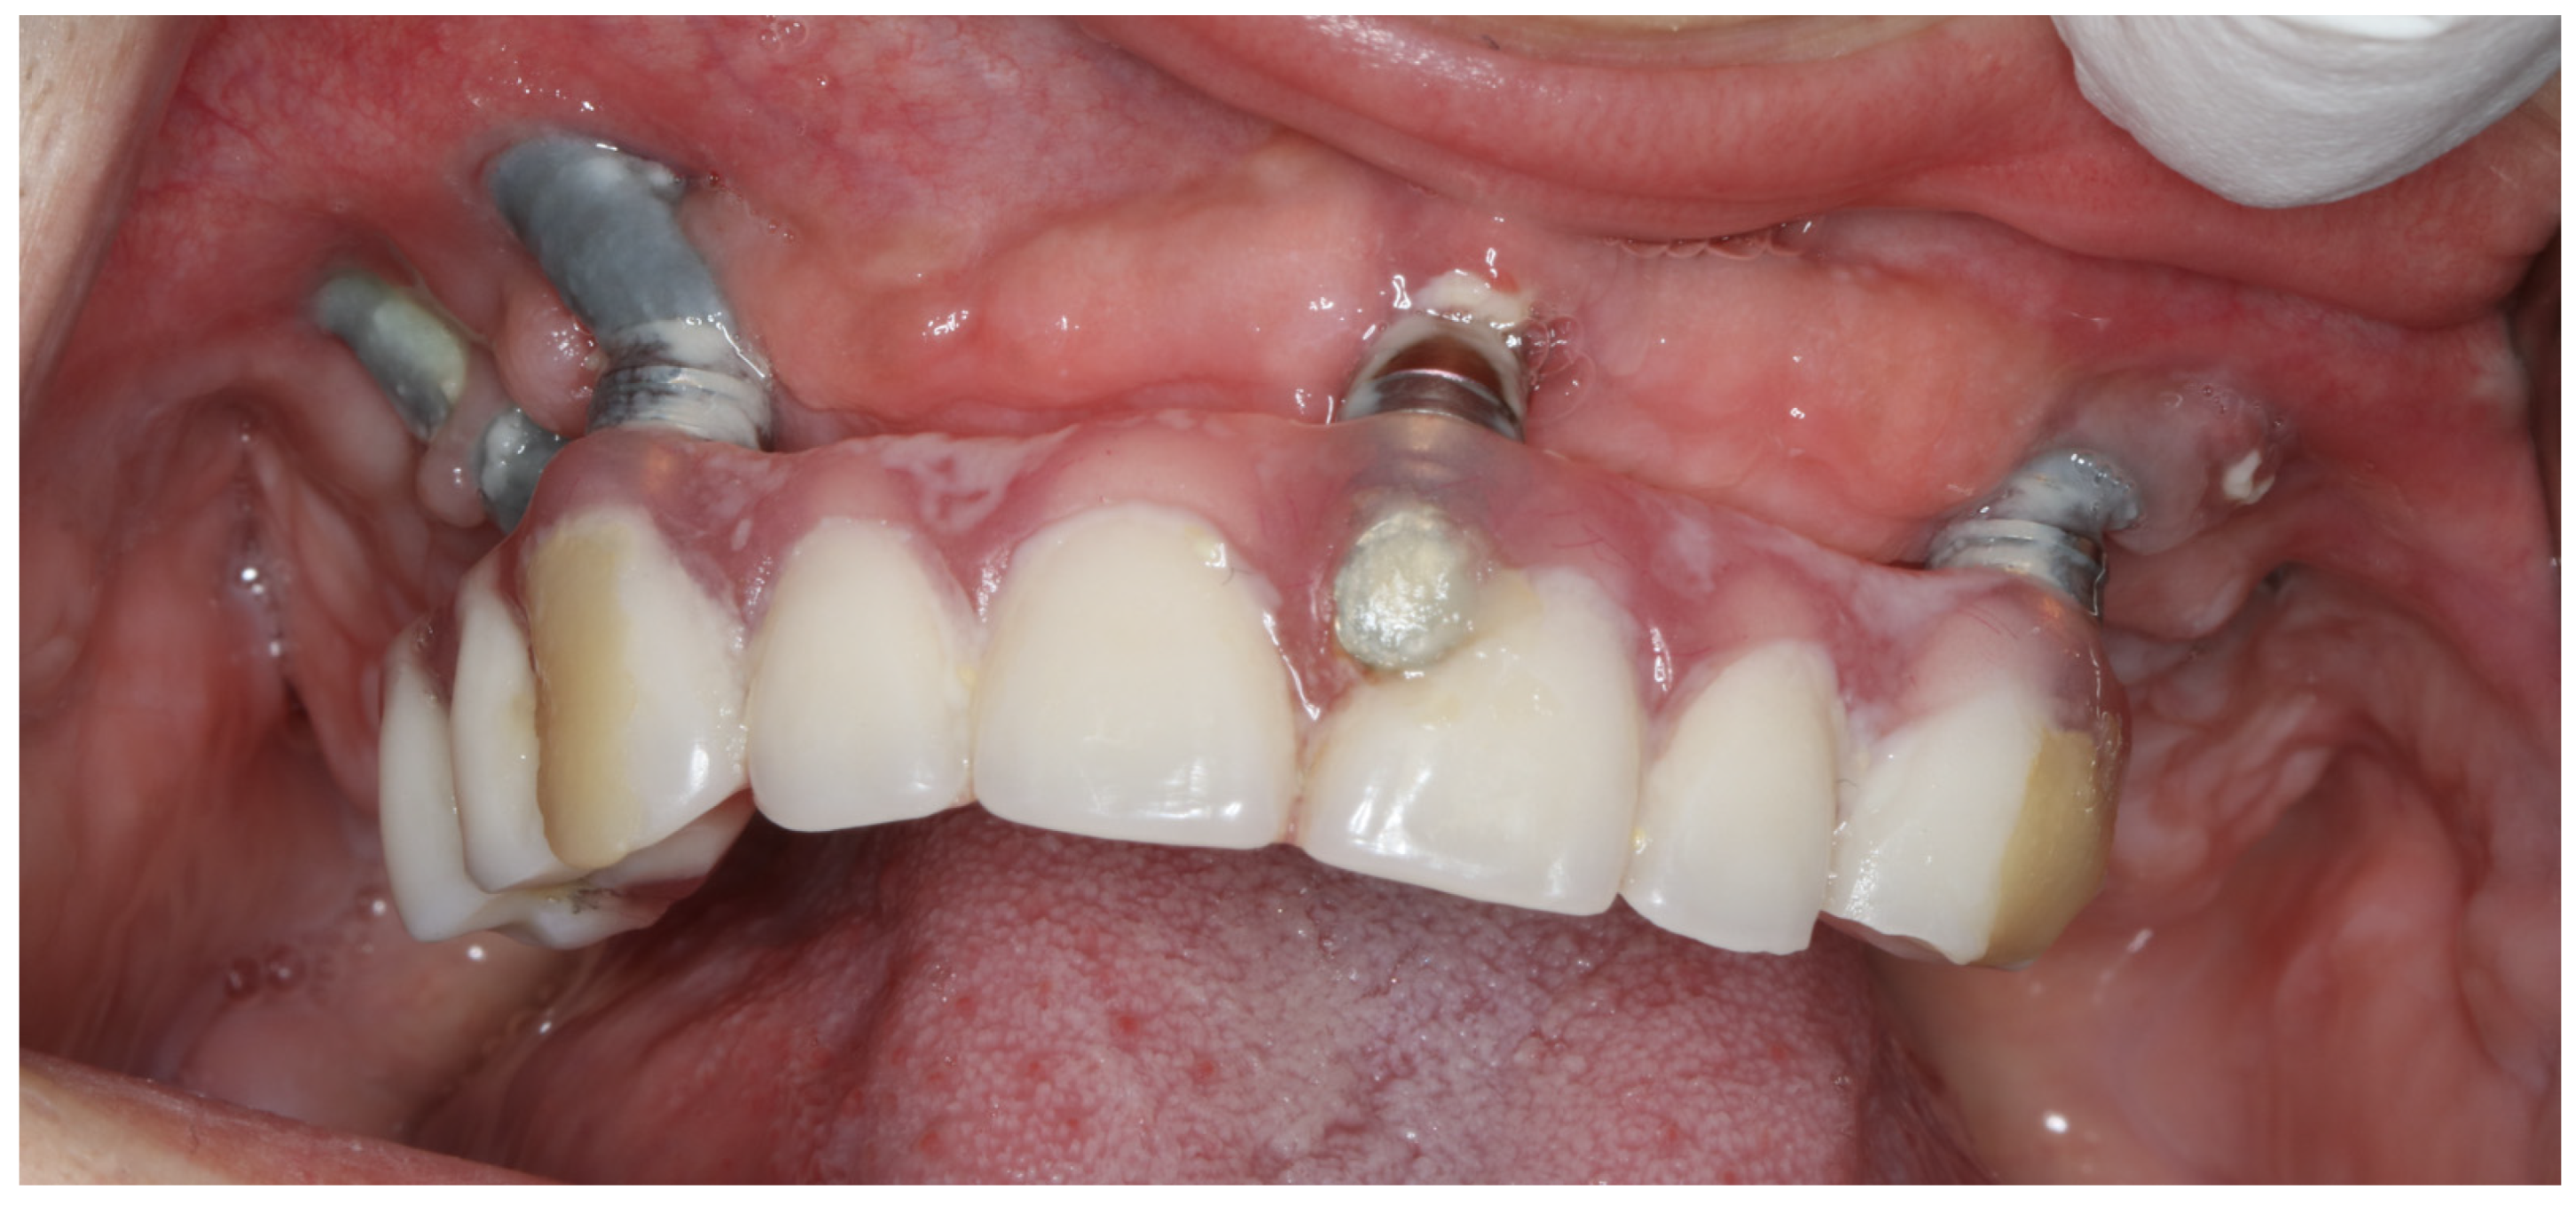

2. Materials and Methods

2.2. Surgery